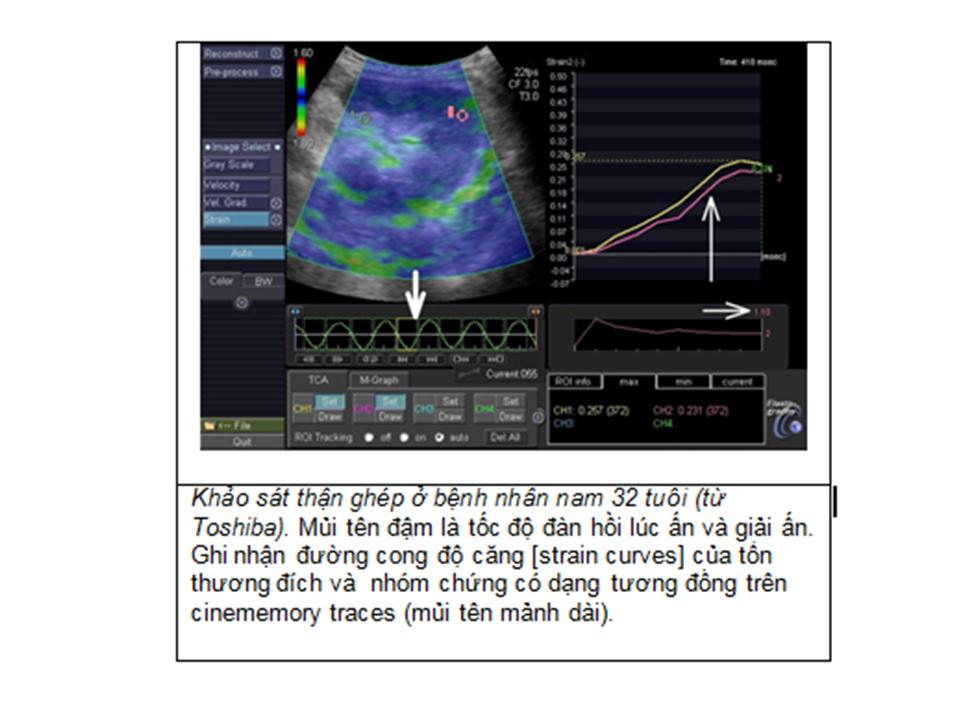

Supersonic Shear Imaging (SSI) được chứng minh có khả năng theo dõi định lượng xơ hóa thận (kidney fibrosis) trên chuột và sau đó, được áp dụng trên người. Có các nghiên cứu với đầu dò cong và bản đồ đàn hồi nhày (viscoelastic properties) của thận người ghép ở cơ thể sống và đối chiếu với sinh thiết.

Một nghiên cứu theo dõi trong 8 tuần trên nhóm 50 chuột bị làm xơ hóa vi cầu thận (glomerulosclerosis) bằng L-Name nhằm khảo sát độ chính xác của kỹ thuật. Bản đồ đàn hồi định lượng của vỏ thận được thực hiện với đầu dò linear 8 MHz. Còn trên thận người ghép, bản đồ đàn hồi định lượng của vỏ thận được thực hiện với đầu dò cong 2,5MHz.

Kết quả trên động vật cho thấy có sự gia tăng độ đàn hồi vỏ thận từ 9-25kPa. Kết quả được đối chiếu với mô học như tiểu đạm và/hoặc định lượng xơ hóa với 3 màu.

Trên thận người ghép có 3 nhóm được khảo sát: nhóm chứng, nhóm đối tượng thận ghép không hoạt động sớm và nhóm thận ghép không hoạt động muộn. Kết quả thu thập được ở 49 bệnh nhân với bản đồ đàn hồi ở sâu 8cm và rộng 10cm cho thấy độ đàn hồi thay đổi giữa các nhóm, tăng từ 9 đến 50kPa. Đối chiếu với mô học đạt được sự thống nhất về các dấu hiệu xơ hóa và độ đàn hồi. Như vậy, độ đàn hồi có liên quan với xơ hóa thận.